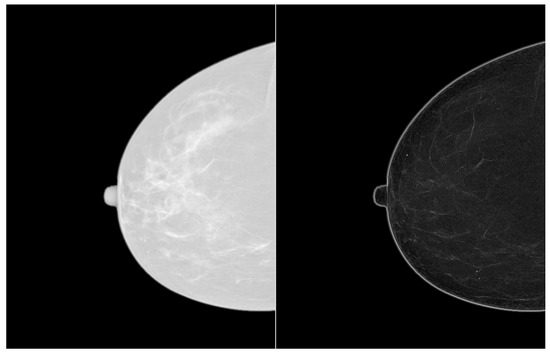

Filtering of Mammograms Based on Convolution with Directional Fractal Masks to Enhance Microcalcifications

1. Introduction